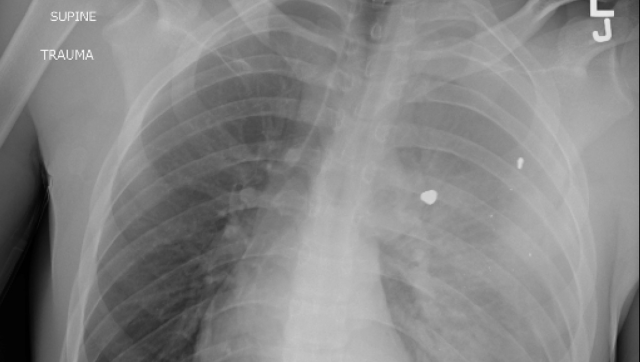

A doctor in US working in an emergency has issued a concerning alert about the primary reason for fatalities among youngsters and adolescents in the United States. Dr. Sam Ghali recently posted an X-ray image on X (previously known as Twitter) depicting the chest of a young boy afflicted by a condition that has now claimed the position of being the chief cause of demise for kids and teenagers in the US. Dr. Ghali posed a question to his followers: “Can you determine the diagnosis?” The image exposes the child’s chest, revealing what seems to be foreign objects lodged within the lungs. “Any guesses? Prayers? To give you a hint, it’s not the FLU, RSV, or COVID,” supplemented Dr. Ghali.

Here’s the Chest X-Ray of a young boy suffering from a condition that is now the #1 cause of death in children and adolescents in the U.S.

Many of the responses accurately guessed that the image portrayed a gunshot wound. A recent analysis of data from the US Centers for Disease Control (CDC), which was published last week, reiterated that gunshots persist as the predominant cause of death for children in the US during 2021. This research, unveiled in the journal of the American Academy of Pediatrics, brought to light that 4,752 youngsters and adolescents (spanning from newborns to 19-year-olds) lost their lives due to gunshot injuries in 2021. Among these cases, approximately 64% were classified as homicides, nearly 30% as suicides, and 3.5% stemmed from “unintentional injury”. These statistics signify a notable surge of 41.5% in the rate of firearm-related deaths in the pediatric population from 2018 to 2021. “The significant rise in firearm-related deaths among children in 2020 garnered widespread attention, with many speculating that the increase could be attributed to the onset of the 2019 coronavirus disease pandemic and the exacerbation of underlying causes,” elucidated the authors. “Remarkably, even though the initial pandemic-induced fears and anxieties have subsided, firearm-related fatalities continued to hold their position as the foremost cause of death for children and adolescents in 2021.” Up to this point in the current year, data amassed by the Gun Violence Archive indicates that no fewer than 1,187 children and teenagers (ranging from newborns to 17-year-olds) have fallen victim to shootings.